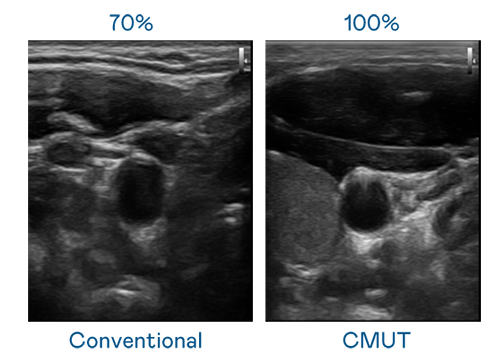

CMUT 技术是一种用电容式微机电元件来产生超音波讯号的技术。与传统 PZT 压电式技术相比,CMUT 频宽增加 30%,更宽频的超音波讯号让影像解析度大幅提升,是实现高影像品质医疗超音波扫描、促进精准医疗发展的关键技术。

大频宽带来超清晰影像

超音波影像的解析度高低,首先取决于探头能发出的讯号频宽。28圈 CMUT 可提供高清晰的超音波讯号,提供高频宽、高灵敏度、影像纹理细节更高的超音波影像,协助医护人员缩短影像判读时间及利用精准的医疗影像进行诊断。